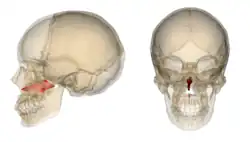

Vômer em vermelho, ao centro do crânio.

Vômer em vermelho, ao centro do crânio. -